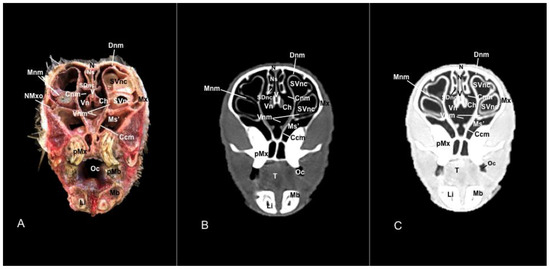

3.1. Anatomical Sections

3.2. Computed Tomography (CT)